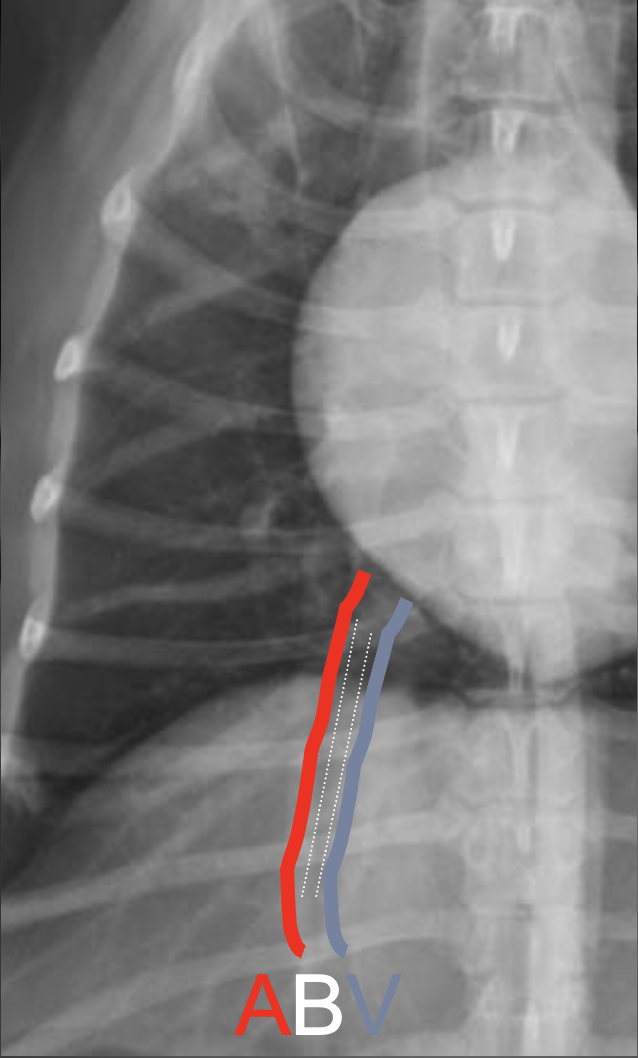

Which structures are outlined in these images?

A

white: aorta

blue arrows: caudal vena cava

What are the characteristics of the caudal vena cava?

-maximum normal diameter is approximately the same as the aorta

-will vary in diameter with cardiac cycle and phase of respiration

-if consistently small, think hypovolemia or shock

-if consistently large, think congestive heart failure